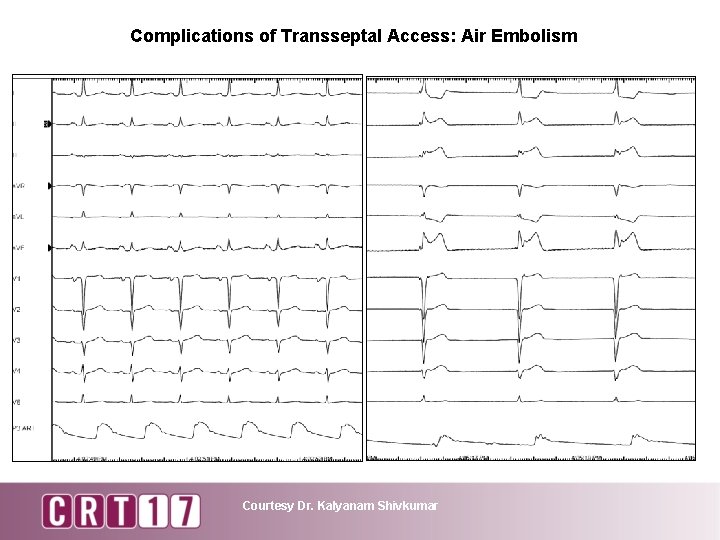

Complications of Transseptal Access: Air Embolism Courtesy Dr. Kalyanam Shivkumar